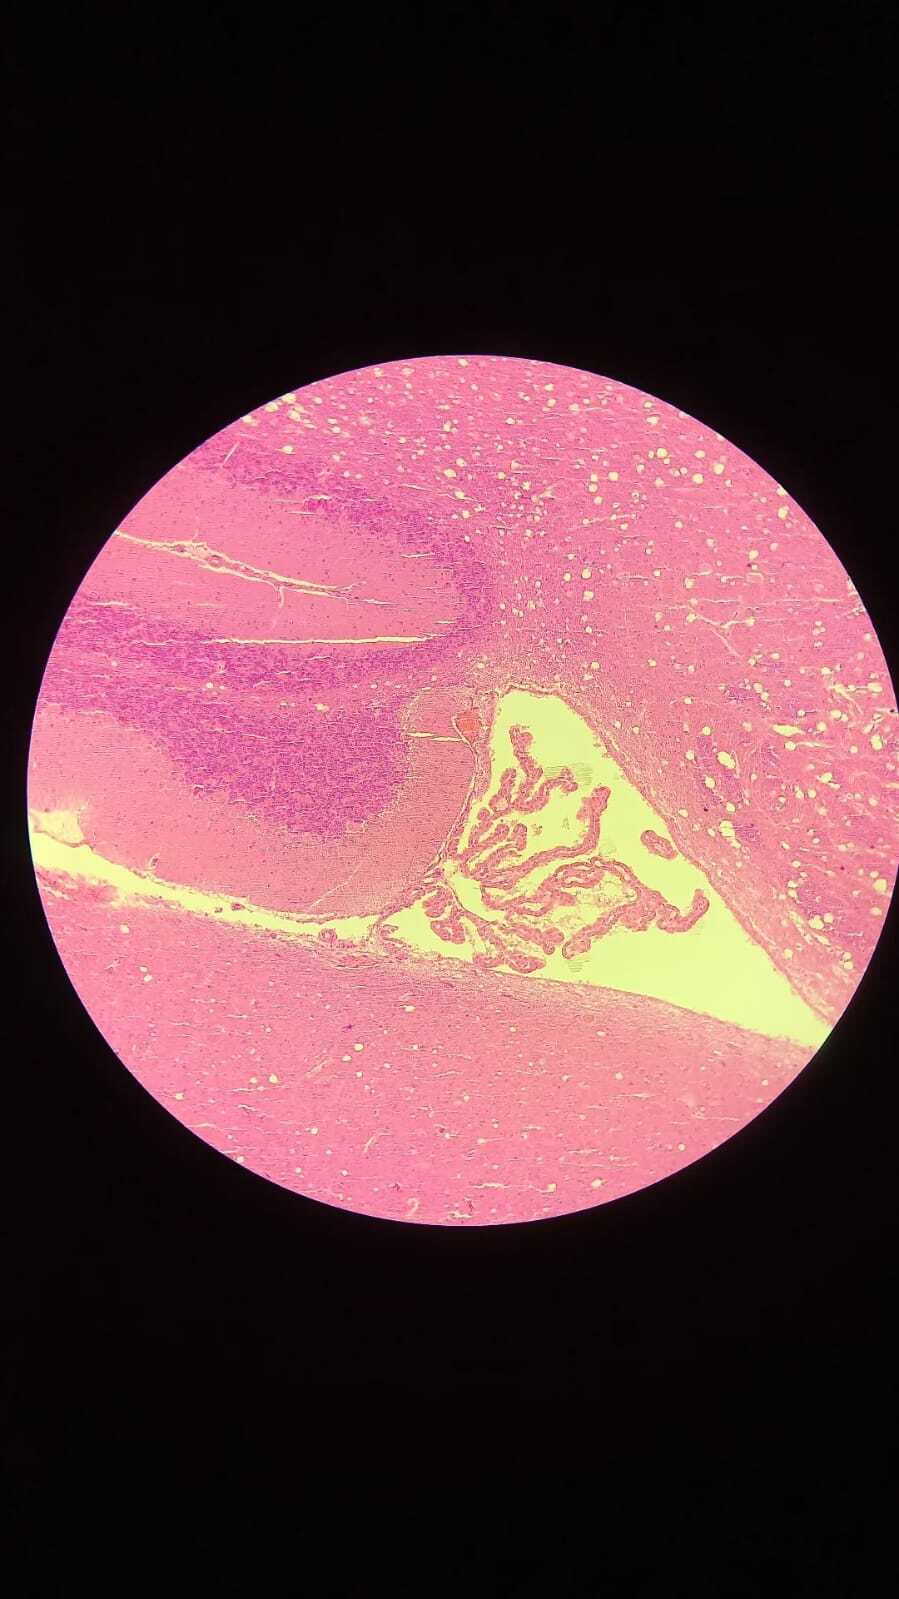

4

Q

Identifique;

Órgão:

Quais estruturas te auxiliaram até a conclusão:

A

Órgão: Cérebro e Cerebelo.

Quais estruturas te auxiliaram até a conclusão: Cerebelo (camada molecular, camada central, camada granular), Cérebro (Anterior), Plexo coróide.